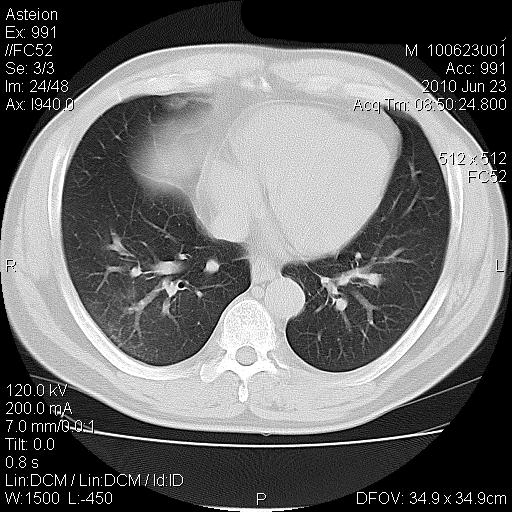

标题: CT27299:胸部CT发热 38-39度

男 41岁 因发烧38-39度 这几天消炎治疗

化验结果 中性粒细胞比率升高(80.9) 淋巴细胞比率下降(10.2) 红细胞压积下降(33.4)

血小板平均分布密度升高(18.9)

双肺炎性灶【密度高 局限 考虑金葡菌 产血浆凝固酶所致】

病灶位于两上肺及右肺下叶背段,建议抗炎治疗后复查;结核不排外。

双肺炎性渗出病变,以右下肺为著。考虑金葡菌感染。

两肺多发结节斑块影,右下见支气管气相,支持两肺多灶性感染,抗炎治疗后复查。

双肺多发大小不等的团片状病灶,周围较模糊可见晕征,未见明显分叶征,纵膈淋巴结未见肿大。

考虑炎性病变。

双肺多发大小不等的团片状病灶可见于肺部炎性肉芽肿,也可见于肺淋巴瘤、肺淋巴瘤样肉芽肿、肺结核、肺部肿瘤,本例的影像表现结合临床考虑肺部炎性病灶。

耐甲氧西林金黄色葡萄球菌生长

敏感:头孢哌酮、舒巴坦、头孢曲松、头孢噻肟、阿齐酶素

耐药:万古霉素、笨唑西林、

患者消炎治疗(第三代头孢类)两周后复查ct片

两肺上叶及右肺下叶感染性病变;建议抗炎治疗后复查。结果消炎吸收